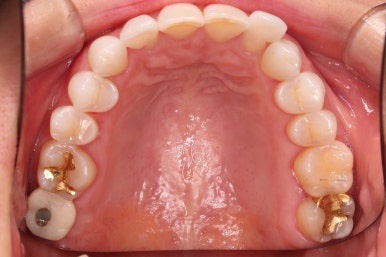

윗니에만 장치를 부착하고 부분교정을 시작했습니다.

환자분이 연산동부분교정 선택하신 장치는 엠파워 클리어라고 하는 자가결찰 세라믹 장치입니다.

장치 부착한 모습 참고해 주시고요.

적절하게 치간삭제를 일부 동반하여 빠른 시일 내에 가지런하게 해드리고 마무리를 했습니다.